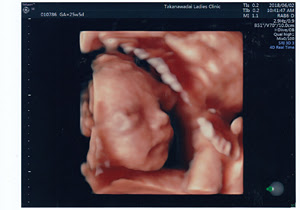

Oct 25, 18 · 4Dエコーは、妊娠週数で見え方が変わってきます。 4Dエコーの映像が見やすい時期として、多くの病院が推奨しているのが妊娠17~34週頃です。 中でもおすすめなのは、4Dエコーの映像に全身がバランスよくおさまる妊娠24~30週頃です。Jan 12, · 妊娠12週目エコー写真と胎児の大きさと 流産の壁の実際 妊娠初期 妊娠中の少量飲酒で 新生児の顔が激変 することが判明 こんな顔になる ソトス症候群の特徴 顎 赤ちゃんなのに小さく尖った顎を持つ顔立ちApr 05, 21 · その検診の内容は、経腹超音波・胎児スクリーニング・助産師外来でした。 いつものように経腹超音波を行い、頭の大きさ・太ももの骨の長さ・心拍・体全体の確認を5分程度実施。この日、顔立ちがはっきりと見えて思わず笑顔に!

妊娠22週(22w)頃は、胎児の顔立ちがはっきりしてくる 妊娠22週(22w)頃の赤ちゃんの皮膚は、赤みがかかり、やや透けて見えるものの、かなり厚くなってきています。 顔には、まゆ毛やまつげが生え、上下のまぶたも整います。 ようやく顔立ちがはっきりとしてきます。 つめも完全にできあがって、伸び続けています。Aug 06, 16 · その考え方によると、胎芽が、細胞の集まりから子どもだと判断され る境界を越えるのはいつかね?いつも(62%)、子どもが何かしたとき、親として何かできたとき(55%) q 大変だなあと思うとき 病状およびそれに関連した医療ケアの負担(67%)、家族生活への負担(28%)、 大変とは思わな